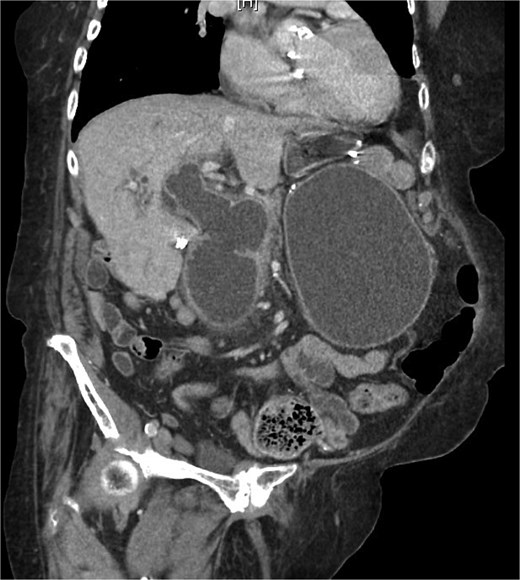

On examination, she was afebrile and hemodynamically stable. Her abdomen was mildly distended with epigastric tenderness and firmness. Laboratory workup revealed moderate leukocytosis (13.3 × 109/l), elevated lipase (288 U/l), and normal total bilirubin (0.8 mg/dl). Contrast-enhanced computed tomography (CT) demonstrated distention of the remnant stomach, duodenum (biliopancreatic limb), CBD, and intrahepatic ducts. A 9.0 × 3.4 cm heterogeneous mass was visualized in the duodenum, consistent with an obstructing gallstone (Figs 1–3).

(a and b) CT demonstrating gallstone in D3-D4 with BPD limb obstruction.